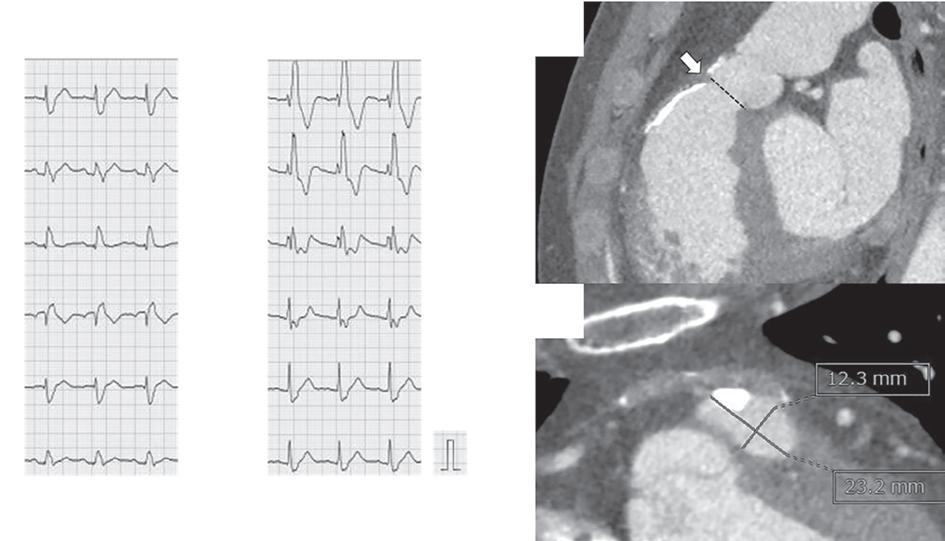

A 57-year-old man presented with a three-decade history of recurrent episodes of palpitation with alarming jugular venous pulsation, but without syncope. Each episode spontaneously reverted to the normal sinus rhythm 6–8 hours after the onset. Cardiac auscultation raised the suspicion of underlying rheumatic mitral stenosis. A 12-lead ECG was suggestive of a WPW pattern with a right posterior septal accessory pathway (Figure 1A). A chest X-ray in the posterior–anterior view was consistent with cardiac auscultation (Figure 1B). A transoesophageal echocardiogram confirmed rheumatic mitral stenosis (Figure 2A and Supplementary Material Video 1). The pliable mitral valve area was 0.8 cm2 and the mean gradient was 17 mmHg at a heart rate of 87 BPM. The coronary angiogram was normal.

The day before the procedure, the patient developed an episode of palpitation during the clinical round. A 12-lead ECG revealed atrial flutter with right bundle branch aberrancy on metoprolol succinate (Figure 2B). The patient’s blood pressure was 124/80 mmHg. Oral verapamil was initiated and the atrial flutter reverted to normal sinus rhythm.

On the day of the procedure, the first balloon mitral valvotomy was performed from a right femoral approach using a 23–26 mm Accura balloon (Vascular Concepts) after transeptal access using an 8 Fr SL-1 sheath and a BRK-0 needle (St Jude Medical). A transeptal puncture was performed after proper needle tip position was confirmed by fluoroscopy (right anterior oblique, left anterior oblique and 90° lateral views) and transoesophageal echocardiography (bicaval and short axis views; Figure 3A). The mean left atrial pressure prior to the valvotomy was 31 mmHg. The balloon was inflated to 26 mm in the right anterior oblique 20° position under fluoroscopy (Figure 3B) because the patient was 160 cm tall. The mitral valve area increased to 2.2 cm2 without any additional mitral regurgitation, and the mean left atrial pressure decreased to 12 mmHg without any mitral valve gradient. Immediate transthoracic echocardiography showed that the mitral valve gradient had decreased to 7/2 mmHg with negligible mitral regurgitation.

Because the patient had baseline pre-excitation through the right posterior septal path and atrial flutter with orthodromic conduction with right bundle branch aberration, one decapolar catheter in the coronary sinus and a quadripolar catheter in the right ventricle were used to study the effective refractory period (ERP) of the accessory pathway rather than using the routine four electrophysiology catheters (three quadripolar [high right atrial, His bundle, right ventricle apex] and one decapolar catheter in the coronary sinus; Figure 4C). The supra-His conduction time was 65 ms and the infra-His conduction time was 9 ms. The baseline ECG was suggestive of a right posterior septal pathway. Right ventricular pacing showed eccentric conduction up to 450 ms, which suggested a retrograde pathway ERP of 450 ms. On pacing the integrated pathway, the ERP was found to be 450 ms. Due to the weak nature of the accessory pathway, ablation was not performed. On rapid atrial pacing, atrial flutter with right bundle branch aberrancy was induced, similar to the clinical tachycardia observed earlier. Ablation for the atrial flutter was not performed, and the patient was maintained on metoprolol succinate and an oral anticoagulant

Figure 1: ECG and Chest X-Ray

Report confirmed by I II IR aVR V1 V2 V3 V4 V5 V5 aVL aVP A B A: A 12-lead ECG showing the Wolff–Parkinson–White pattern with a possible right posterior septal accessory pathway because the R/S ratio is <0.5 in V1 and V2 and <1 in the inferior leads. B: Chest X-ray in the posterior–anterior view showing mitralisation of the left heart border, double atrial shadow on the right

side and a horizontal left bronchus. A: There was significant mitral stenosis and the mean mitral valve gradient of 16 mmHg prior to the balloon mitral valvotomy. B: Atrial flutter with 2:1 atrioventricular block and right bundle branch aberrancy was evident during the electrophysiological study by pacing the atria with a decapolar catheter in the coronary sinus at cycle length of 200 ms.

Figure 4: Electrophysiology Study to Map the Accessory Pathway

Figure 3: Transsepetal Puncture for Balloon Mitral Valvotomy and Electrophysiology Study in One Go A: Septal puncture using fluoroscopy and transesophageal echocardiography guidance. B: A 23–26 mm Accura balloon was inflated to 26 mm in the right anterior oblique view. Electrophysiological study using one quadripolar catheter for right ventricle pacing and one decapolar catheter in the coronary sinus.